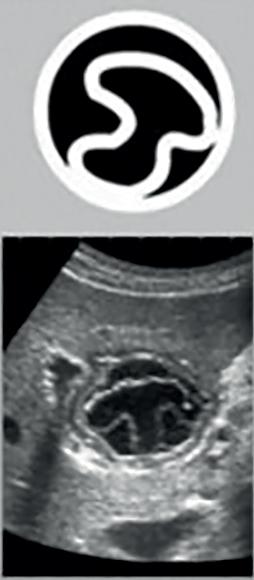

The Positive Effect of Water Immersion on Labor Progress Assessed by Intrapartum Ultrasound Examination

Pozytywny wpływ zastosowania immersji wodnej na postęp porodu oceniany metodą ultrasonografii śródporodowej